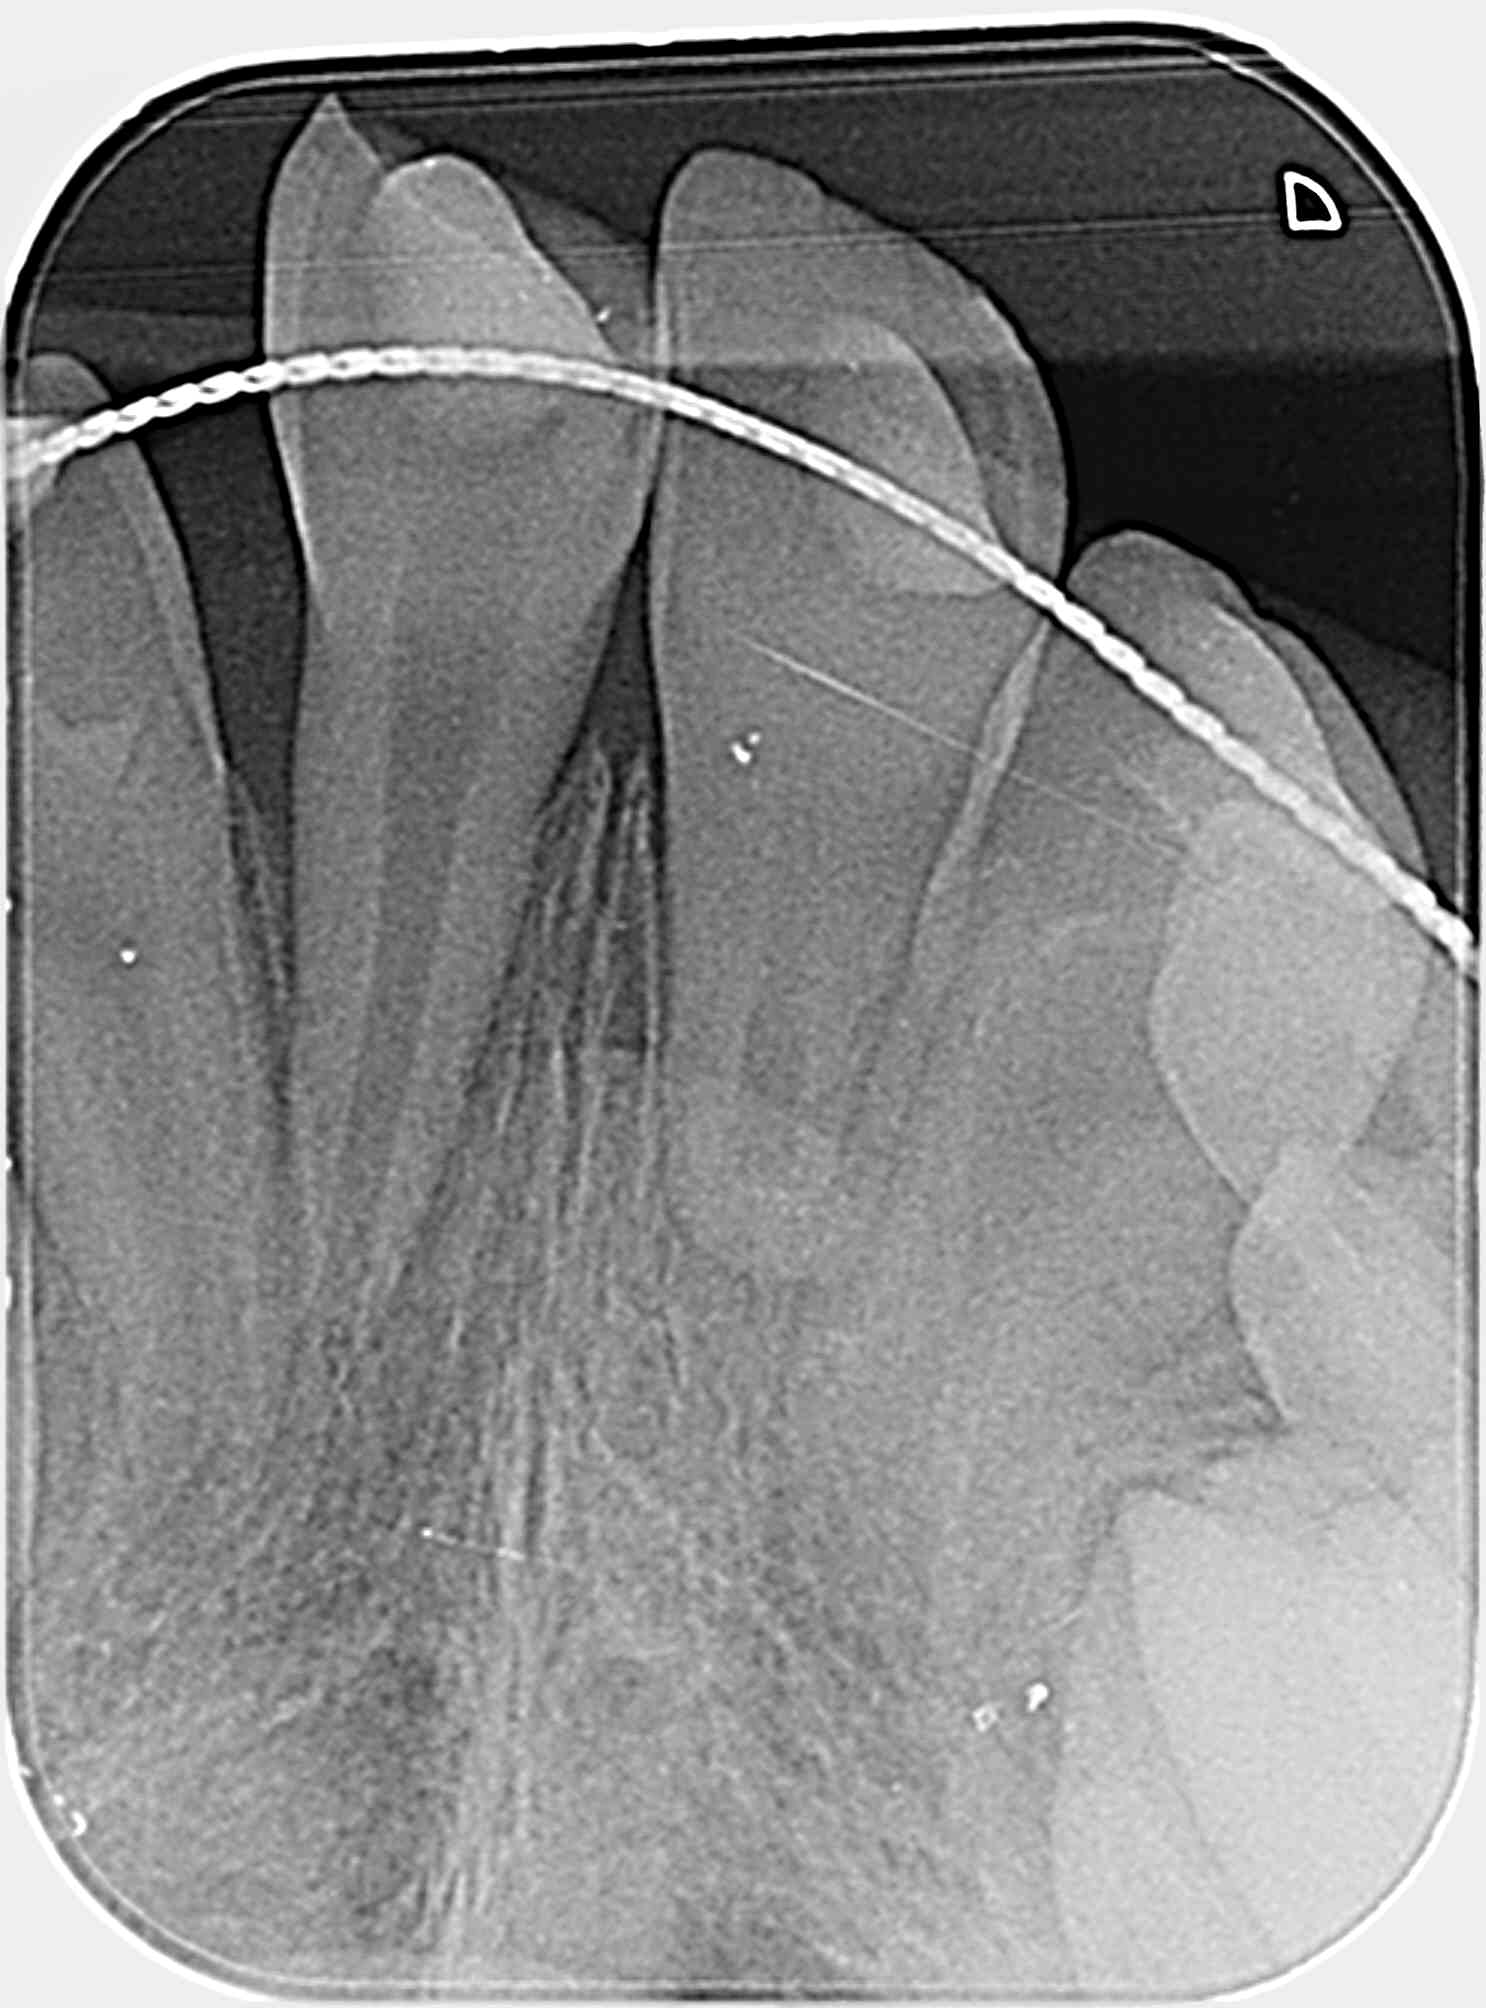

suite à l'expulsion totale et la mise en place tardive de 11.21 en urgence , la radio de contrôle 3 mois après, montre des signes de résorption avec un pronostic sombre , dans le cadre d'une cl 2.1.

La 21 est en résorption rapide.